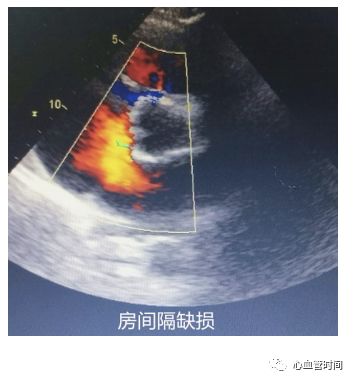

房间隔观察有无过隔血流、膨出瘤及摆动现象。一定要注意区分右房内的

红色血流是起源自下腔静脉还是房间隔,避免误诊。

三尖瓣观察三尖瓣形态及反流情况。

房间隔观察有无过隔血流、膨出瘤及摆动现象。一定要注意区分右房内的

红色血流是起源自下腔静脉还是房间隔,避免误诊。

房间隔当存在

房间隔缺损时,过隔血流因几乎垂直于探头而不易观察,建议可稍微

偏转探头调整血流角度进行观察。

房间隔当存在

房间隔缺损时,过隔血流因几乎垂直于探头而不易观察,建议可稍微

偏转探头调整血流角度进行观察。

剑突下切面

对于一些胸前切面显示不清的患者,剑突下切面可以很好地 作以补充。 房间隔 在患者成像条件良好的前提下,剑突下切面是观察 房间隔缺损的绝佳切面。该切面房间隔相对垂直于探头,可更好的显示 过隔血流,像卵圆孔未闭的几毫米的血流也能轻松显示,且可更好的与腔静脉的血流做区分,明确血流来源。 下腔静脉